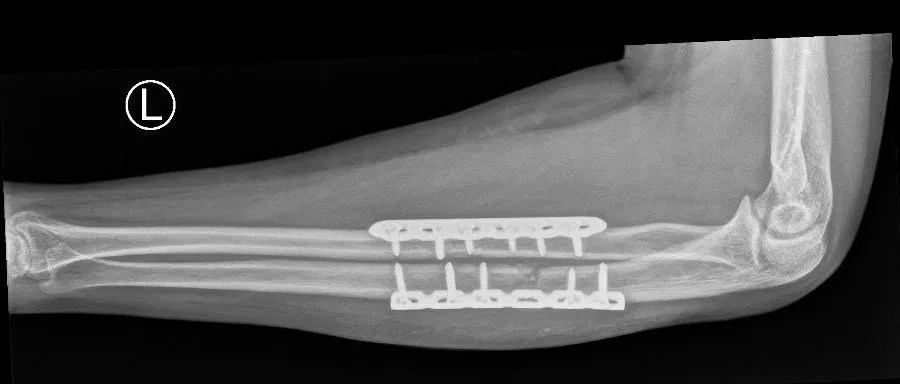

- Ingreep: De chirurg maakt een insnede in de arm ter hoogte van de breuk. Afhankelijk van welk bot (of beide) gebroken is, wordt aan de duimzijde (voor het spaakbeen) en/of de pinkzijde (voor de ellepijp) geopereerd. De botstukken worden nauwkeurig teruggeplaatst. Vervolgens worden ze vastgezet met een plaat en schroeven bij volwassenen (interne fixatie) of met een elastische nagel (TEN-nagel) bij kinderen. Soms wordt bij zeer complexe verwondingen tijdelijk een externe fixator (een uitwendig frame met pinnen door de huid) geplaatst om de botten op lengte en in rustpositie te houden, bijvoorbeeld bij open fracturen.

- Na de operatie: Na een operatieve behandeling van een onderarmfractuur krijgt u een verband en vaak een kunststof spalk of gips voor ondersteuning gedurende de eerste 1 à 2 weken. Hierna start al gauw de mobilisatie: u gaat oefeningen doen om de elleboog, pols en vingers weer in beweging te krijgen. Tillen of duwen met de arm is verboden totdat de breuk genezen is (meestal circa 6 tot 8 weken). Eventuele draden of pinnen van een elastische nagel (TEN-nagel) of een externe fixator worden later weer verwijderd als het mogelijk is.

Stap 2: Operatieve behandeling

- Indicatie voor operatie: Veel onderarmfracturen, vooral bij volwassenen, worden operatief behandeld. Als de botdelen verplaatst zijn of als beide botten gebroken zijn, zal men meestal voor een operatie kiezen. Complexe combinaties (zoals een Monteggia- of Galeazzi-letsel) vereisen vrijwel altijd een operatie om de arm weer goed te krijgen. Met andere woorden, zijn uw spaakbeen én ellepijp gebroken en staan de stukken niet goed, dan volgt een operatie om alles correct te zetten.